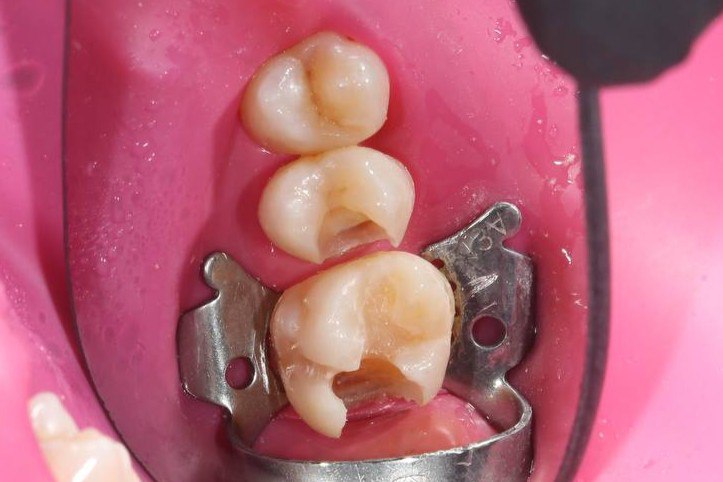

- Композитні пломби

Композитні пломби використовуються для відновлення пошкоджених або каріозних зубів. Вони виготовляються з матеріалів, які ідеально імітують натуральний колір зуба, що дозволяє досягти максимально естетичного вигляду навіть у тих місцях, де пломба не повинна бути помітною.